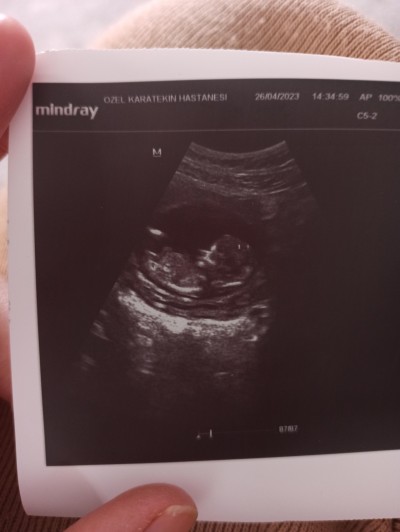

Bugün ikili tarama için muayene oldum yarına gün verdi sizinde tahminlerinizi almak istedim kızçeler

Görür görmez kız diyesim geldi

Erkek bence hayırlısı olsun inşallah eli ayağa düzgün sağlıklı olsun inşallah

Kiz gibi geldi